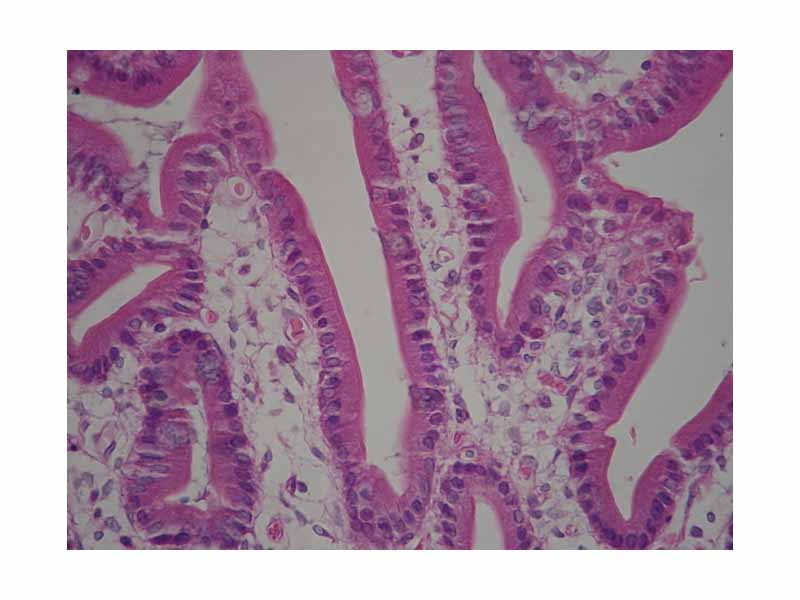

Duodenum with brush border (microvilli)